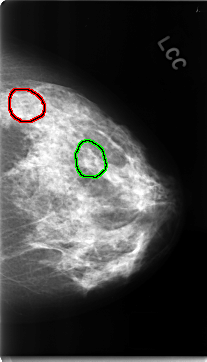

C_0150_1.LEFT_CC

LEFT_CC LINES 4696 PIXELS_PER_LINE 2688 BITS_PER_PIXEL 12 RESOLUTION 50 OVERLAY

FILE: C_0150_1.LEFT_CC.OVERLAY

TOTAL_ABNORMALITIES 2

ABNORMALITY 1

LESION_TYPE CALCIFICATION TYPE AMORPHOUS DISTRIBUTION CLUSTERED

ASSESSMENT 4

SUBTLETY 1

PATHOLOGY BENIGN

TOTAL_OUTLINES 1

ABNORMALITY 2

PATHOLOGY MALIGNANT